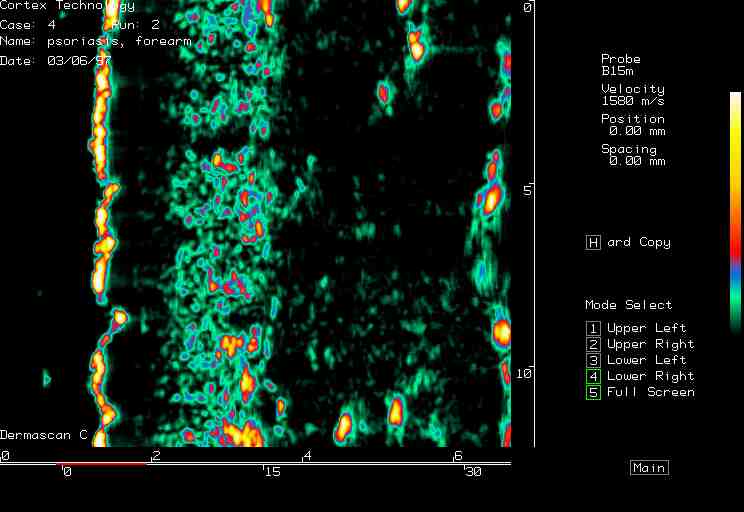

| Steroid atrophy, Psoriasis |  Steroid atrophy, arm |

Psoriasis, arm |